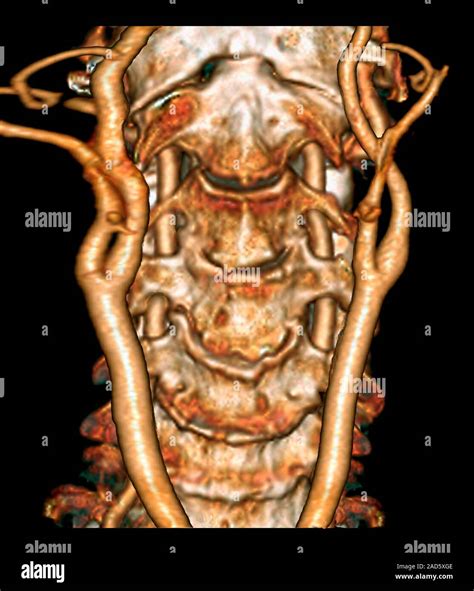

• 3D Reconstruction: This involves generating three-dimensional images of the spine, which can be particularly useful for surgical planning.

• CT Angiography (CTA): This technique uses contrast dye to visualize the blood vessels in the neck, which can be important in cases of vascular injury or aneurysm.